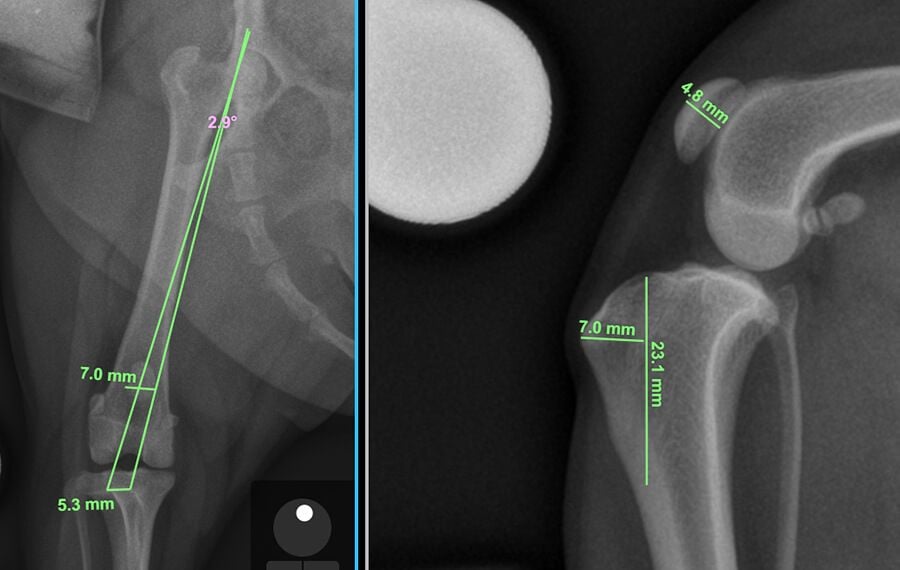

In severe cases, the limb may suffer from Complex Skeletal Malalignment—a multi-level combination of femoral and tibial deformities. In these cases standard procedures are often insufficient. At VSOS, we utilize advanced orthopaedic engineering to address these challenging cases.

If the thigh bone is bowed (a condition known as Distal Femoral Varus), it creates a mechanical pull that forces the kneecap out of place. To fix this, we perform a Distal Femoral Osteotomy (DFO). This procedure involves cutting the femur to straighten its alignment, ensuring the quadriceps mechanism pulls the kneecap in a perfectly straight line.

3D Planning & CT-Guided Surgery

Precision is vital when correcting bone deformities. We utilize high-resolution CT scans to create a three-dimensional map of your pet's limb. In complex cases, we use this data to design3D-printed, patient-specific cutting guides. These custom-made tools fit onto the bone during surgery, allowing our specialists to execute corrective cuts with sub-millimetre precision, tailored exactly to your pet's unique anatomy.